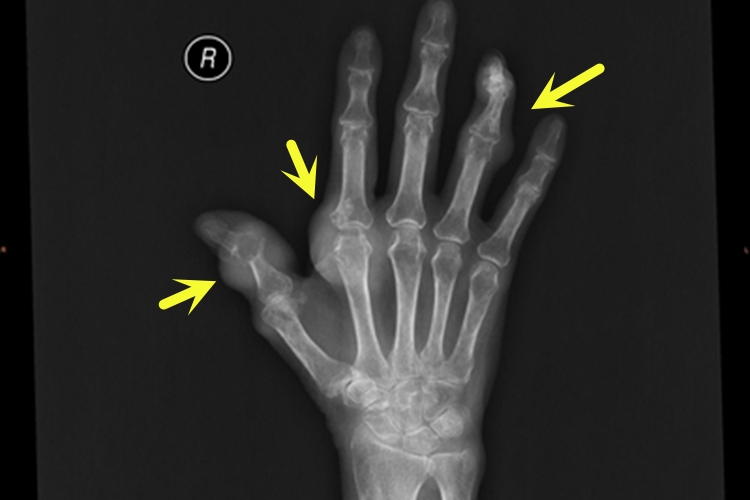

痛风患者手部会出现红肿、疼痛,有不规则状凸起,影像学显示患者手上部分关节处出现团状白雾样的物质,多为痛风引起的痛风石。